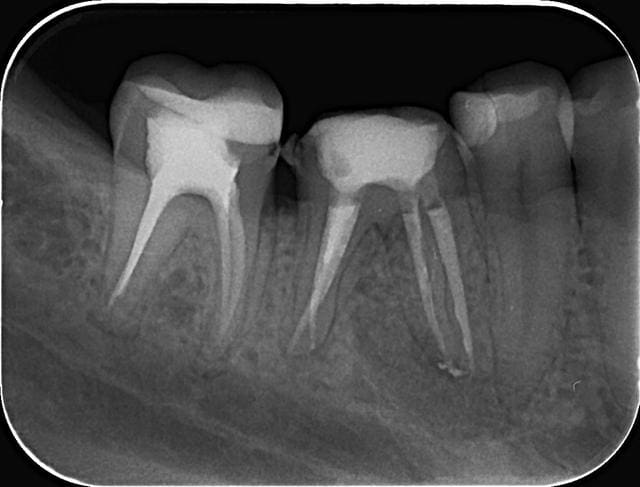

46 - fig 1,2 situation initiale

Fase du traitement: seule visite 2h

- percussion - positive

- teste du vitalité - négative

NaOCl 5% - l'irrigation et l'activation par ultrasons

chaud condensation de gutta-percha

build-up

Apres obturation - fig.3,4

Apres 8 mois

Fig.5,6